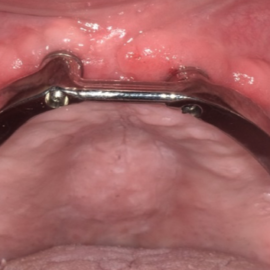

The process of implant dentures begins with a thorough dental examination and consultation with a dental implant specialist. During this visit, different options are discussed, and a personalized treatment plan is created based on your needs and medical history.

Receiving implant dentures is a multi-step process that includes placing the dental implants and securely attaching the dentures with precision.